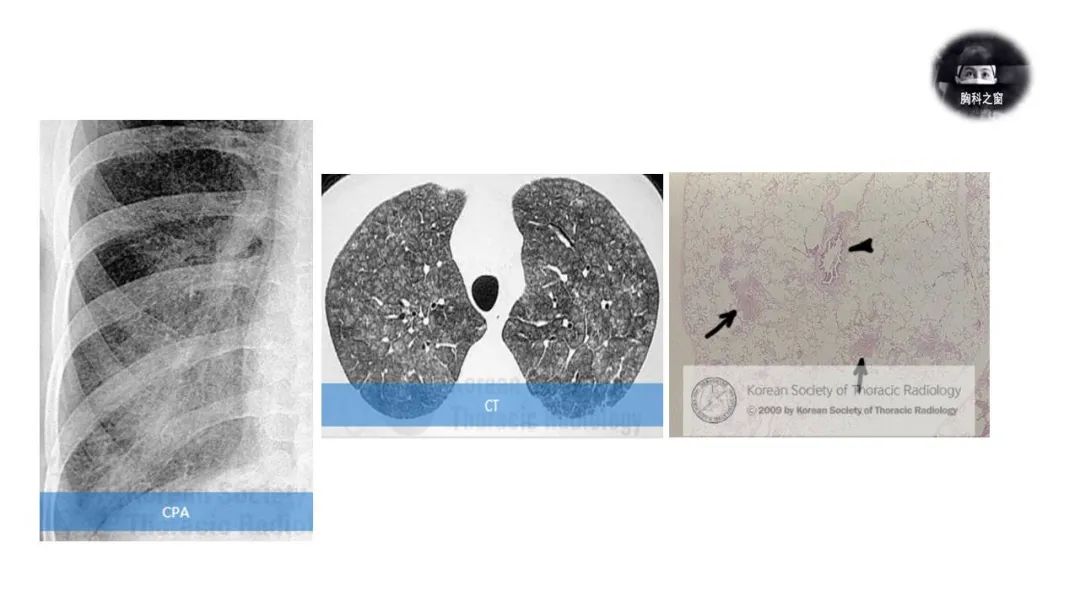

1.急性期:弥漫性界限不清的气腔实变/磨玻璃影。 病理上,多形核细胞、嗜酸性粒细胞和淋巴细胞的肺泡充盈。

2. 亚急性期:细小结节状分布,呈支气管周围分布。

3.慢性期:斑片状纤维化。